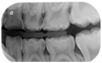

- Case 1: arrested deep carious lesions (ICDAS 6) on first primary molars (74, 84) in a preschool child;